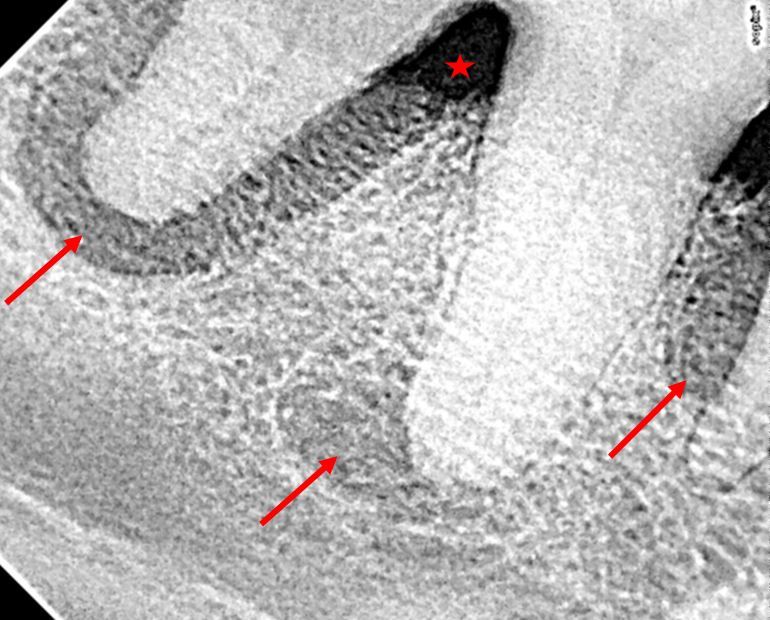

Daraufhin wurde eine Inhalations-Narkose mit entsprechendem Monitoring (Beobachtung, Überwachung) eingeleitet, und die Maulhöhle konnte genau untersucht und die Befunde dokumentiert werden. An beiden rechten Reißzähnen (P4 Oberkiefer und M1 Unterkiefer) und weiteren drei Backenzähnen im rechten Unterkiefer (P4, M2, M3) und eines weiteren Oberkiefer Backenzahnes (P2) war ein massiver Rückgang des hochgradig entzündeten Zahnfleisches (Gingivitis mit Gingivarezession) zu erkennen. Diese Zähne waren hochgradig von Zahnstein bedeckt. Neben tiefen Zahnfleischtaschen waren offene Wurzelgabelungen an den teilweise leicht gelockerten Zähnen zu sondieren. Eitrige Auflagerungen im Bereich der Zahnwurzeln (Konkrement) und Blutungen aus den Zahnfächern waren zu beobachten. Es wurden mehrere intraorale Röntgenbilder angefertigt, und deren Befund (Knochenabbau am Kiefer und Wurzelgranulome) rundete die Diagnose einer hochgradigen, lokalen Parodontitis, einer Entzündung und Lockerung des kompletten Zahnhalteapparates, ab. Die Reißzähne wurden per „offener Extraktion“ gezogen und die gesäuberten Extraktionswunden wurden mittels eines Zahnfleischlappens mit resorbierbarem Nahtmaterial verschlossen. Die anderen betroffenen Zähne konnten ohne chirurgische Eröffnung des Zahnfaches gezogen werden. Auch bei dieser „geschlossenen Extraktion“ erfolgte eine Wundtoilette mit anschließendem Wundverschluss. Die restlichen, als unauffällig eingestuften Zähne wurden zuerst manuell, dann mit Ultraschall-Scaler gereinigt und anschließend poliert.